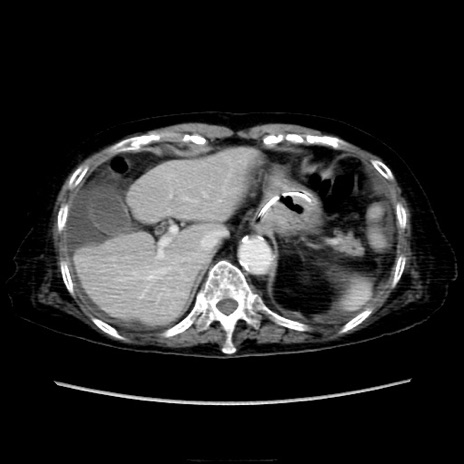

症例40(横断像)

【症例】90歳代女性

【主訴】腹痛・嘔吐

【現病歴】 食欲低下、嘔吐があり昨日他院受診。肺炎と診断され入院となる。入院後より腹部全体に圧痛あり。胃管留置され経過みていたが、症状持続するため、

当院転院となる。

【既往歴】胸椎圧迫骨折、胆石症

【身体所見】腹部:中央に激痛あり、圧痛あり、反跳痛不明

【データ】WBC 17100、CRP 18.82

他院CT

横断像